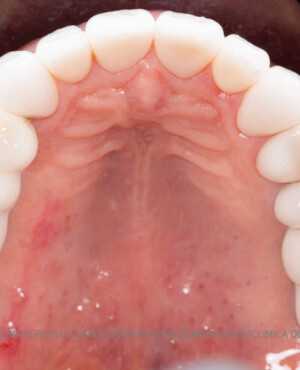

Adiția de gingie (gingivoplastia)

Aditia gingivală este o procedură chirurgicală ce corectează diverse probleme estetice și funcționale, cum ar fi recesiunea gingivală. În implantologia modernă, aditia de țesut moale este utilizată aproape în fiecare intervenție de inserție a implantului dentar pentru a asigura un aspect estetic natural și o bună integrare a implantului în cavitatea bucală.